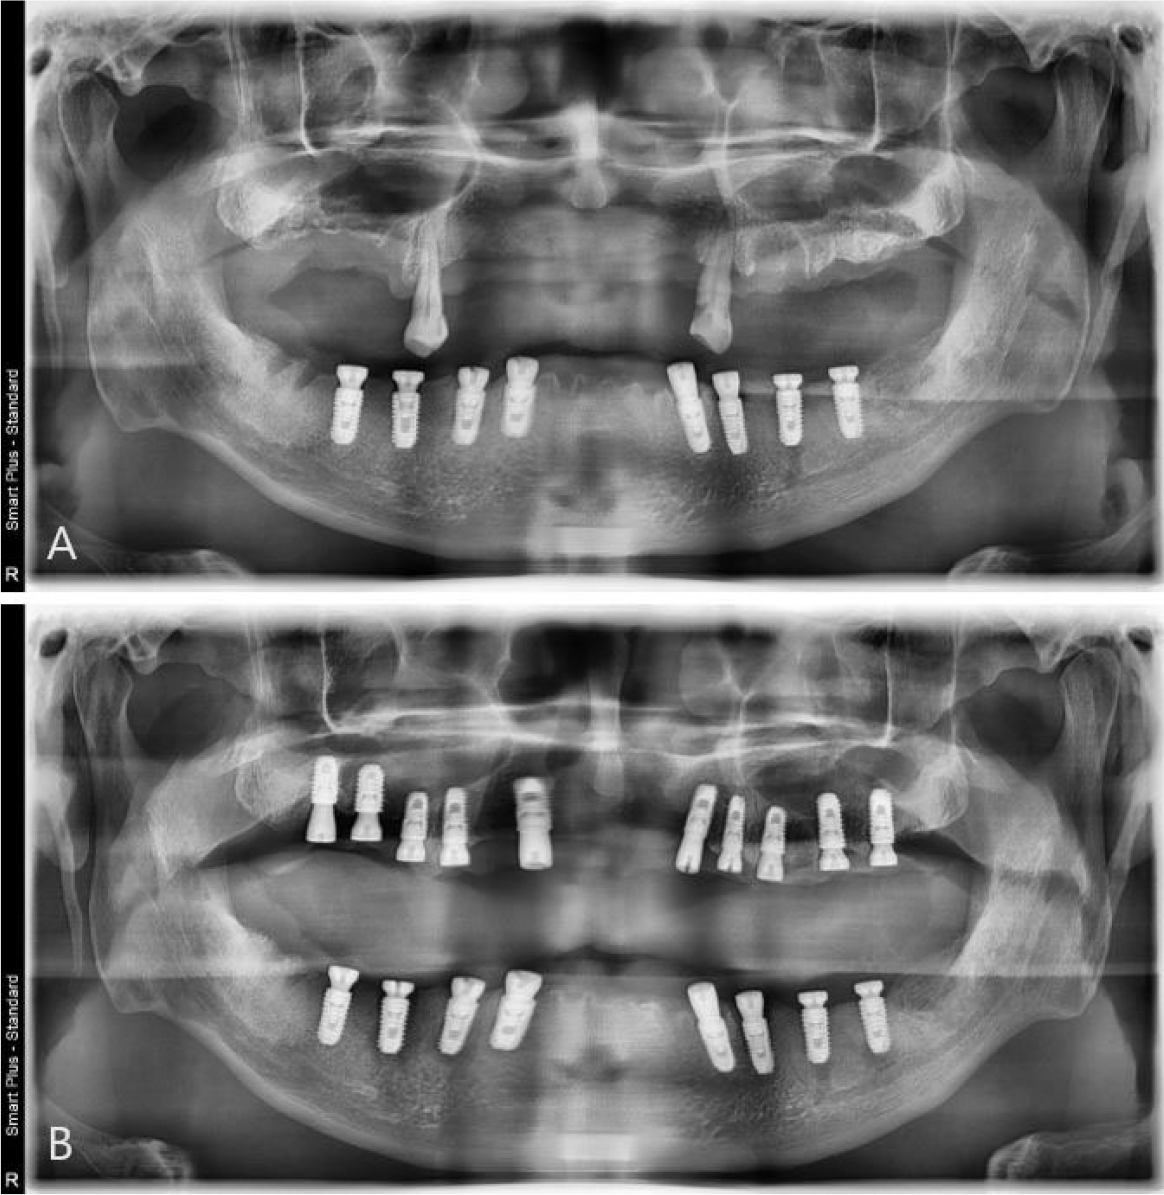

As a result, the following treatment plan was established: (a) extraction of the remaining teeth in the maxilla and mandible, and (b) implant placement using implant surgical guides. Specifically, a total of 10 implants were planned to be placed at the maxillary lateral incisors, canines, first premolars, first molars, and second molars on both sides, whereas a total of eight implants were planned to be placed at the mandibular canines, first premolars, first molars, and second molars on both sides. Subsequently, it was decided to wait for healing after delivering provisional dentures to the upper and lower jaws. The final prosthesis was designed with three pieces, including one anterior segment and two posterior segments, on both upper and lower jaws.

To overcome the limitations of the mucosal-supported surgical guides in the edentulous area, all teeth, except two teeth for each of the upper and lower jaws, were extracted (Fig. 3). Next, implant surgical guides were designed by superimposing the intraoral scanning data on the remaining teeth as shown in the CBCT images. The diagnostic model was designed by duplicating the initial vertical dimension by superimposing the upper and lower jaw scanning data obtained after extraction from the initial scanning data. In addition, the position of implantation was planned according to the simulated design (Figs. 4 and 5) using the implant planning software (Implant Studio; 3Shape). Subsequently, the second step of the implant surgical guide was designed after virtually extracting the remaining teeth from the scanned data, considering the location of the implants to be placed at the extraction site (Fig. 6). Finally, provisional dentures were designed to maintain the initial vertical dimension (Dental System; 3Shape) (Fig. 7).

During implant surgery, an implant surgical guide was placed on both sides of the canines before extraction of the remaining mandibular canines. Up to this procedure, all implants required for the patient, except canines, were completed successfully (TS-III; OSSTEM, Seoul, Korea). After the extraction of canines on both sides, which were used as supporting components (i.e., anchor teeth) for the implant surgical guide, a second-step implant surgical guide was used to place the implants on the canine areas immediately (Fig. 8A). In addition, provisional dentures were delivered after the surgical procedures. Similar to the mandibular surgery, after the extraction of the supporting teeth for the implant surgical guide, a second-step implant surgical guide was used to place the implants immediately after the extraction (Fig. 8B). Finally, provisional dentures were stably delivered after the surgical procedures. After a 2-month osseointegration period, implant failure was observed in the right mandibular first molar, therefore, the fixture was removed and re-surgery was performed in that area. However, provisional fixed restorations were made using custom abutments and 3-piece polymethylmethacrylate (PMMA) for other successfully healed areas (Fig. 9).